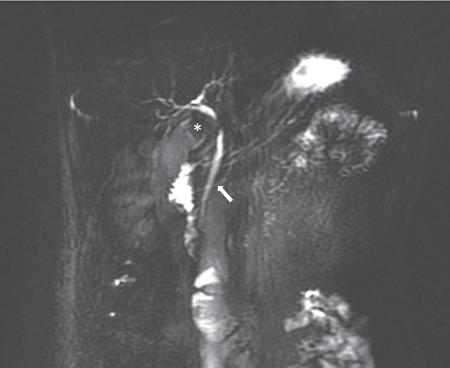

Priscilla Joshi, Mangal Subhash Mahajan, Vandana Jahanvi Imaging is important in paediatric patients with pancreatic pathologies which can be congenital, pancreatitis or neoplastic. Congenital pancreatic anomalies predispose the children to recurrent attacks of pancreatitis and other complications. Paediatric pancreatic tumours are uncommon but when they do occur imaging is essential for their diagnosis, staging and posttreatment follow-up. Pancreas divisum is the most common congenital pancreatic anomaly. It occurs in approximately 4%–14% of population. Failure of fusion of dorsal and ventral pancreatic ducts results in pancreatic divisum. Three variants of pancreatic divisum are known: In most cases, pancreatic divisum is asymptomatic. However, it may give rise to recurrent episodes of pancreatitis. Pancreatitis is believed to occur due to inadequate drainage of pancreatic secretions by the duct of Santorini. Pancreatic divisum is easily identified on MRCP (magnetic resonance cholangiopancreatography) which is a noninvasive technique and therefore is now increasingly being performed over ERCP to avoid ERCP-induce pancreatitis. Secretin-induced MRCP improves the visualization of the pancreatic ducts. The dorsal duct can be seen passing the CBD anteriorly and superiorly on imaging. This entity can also be identified on MDCT if the pancreatic duct is visualized. Rarely, it may be associated with cystic dilatation of terminal portion of duct of Santorini which is called Santorinocele. Failure of rotation of ventral bud along with the duodenum results in encasement of duodenum by a rim of pancreatic tissue and this entity is known as annular pancreas. The band of pancreatic tissue encircling the duodenum could either completely or partially surround the duodenum and is in continuity with pancreatic head. It occurs in approximately 1 in 20,000 population. Not all cases of annular pancreas present in childhood. In paediatric age group, it can present as neonatal duodenal obstruction because of associated duodenal stenosis. Children and adults with annular pancreas may also present with recurrent pancreatitis, postbulbar duodenal ulcerations or biliary obstruction. On upper gastrointestinal studies (barium meal), characteristic narrowing of second part of duodenum is seen. CT and MRI may show rim of pancreatic tissue encircling the duodenum. In partial annular pancreas (Fig. 9.16.2), pancreatic tissue is seen extending posterolateral or anterolateral to the duodenum with the pancreatic tissue giving a ‘crocodile – jaw’ configuration. This in the presence of gastric outlet obstruction helps in the diagnosis of incomplete annular pancreas. MRCP shows the pancreatic duct encircling the second part of the duodenum and entering it over its right lateral aspect. The pancreatic duct draining the annular segment usually drains into the main pancreatic duct. It can also drain into the intrapancreatic portion of common bile duct, the duct of Wirsung or the duct of Santorini. Secretin-induced MRCP because of its ability to demonstrate ductal anatomy well may become the best noninvasive imaging modality for diagnosis of pancreatic ductal variants including annular pancreas. Other causes of paediatric duodenal obstruction should be kept in mind while diagnosing annular pancreas. Other than annular pancreas, the presence of duodenal narrowing on barium study in neonates, should raise the possibilities of duodenal atresia, duodenal web and Ladd’s bands. In duodenal atresia, the contrast does not pass beyond the obstruction and no air is seen on radiograph beyond the atretic segment. Whereas, in annular pancreas, intestinal gas is seen distal to the involved segment. And on upper gastrointestinal studies, the duodenal bulb is distended with slow transit of oral contrast through the stenosed duodenal segment distally. In duodenal web classical ‘wind–sock’ diverticulum is seen due to distal stretching of the web forming an intraluminal pseudodiverticulum. On barium studies, thin radiolucent membrane is seen due to filling of barium within the lumen and around the diaphragm. The mutation in the developmental protein IPF1, results in pancreatic agenesis. It is very uncommon as it is incompatible with life. Anomalies associated with this condition are: foetal growth restriction, agenesis of gallbladder and polysplenia. Hypoplasia or partial agenesis occurs due to nondevelopment of dorsal or ventral pancreatic bud. Partial agenesis of the dorsal pancreas is more common than agenesis of the ventral portion. However, complete dorsal pancreatic agenesis is rare. Dorsal pancreatic agenesis is often associated with heterotaxia syndrome. Partial dorsal pancreatic agenesis is more common than partial ventral agenesis. Complete dorsal pancreatic agenesis is however rare. In partial dorsal agenesis, short rounded head of pancreas is seen adjacent to the duodenum with absence of pancreatic neck, body and tail; however, remnant of duct of Santorini and minor duodenal papilla are generally present. In complete dorsal agenesis, both the minor duodenal papilla and the duct of Santorini are absent. The distal pancreas contains the islet cells, hence those with dorsal agenesis are at a higher risk of developing Diabetes Mellitus. This uncommon condition is diagnosed when there is an accessory lobe of pancreatic parenchyma originating from the main gland and draining through an aberrant duct. The accessory lobe may be of varying size and may drain into the main pancreatic duct through a narrow or a wide communication. Association with gastric duplication cyst is known and if present the aberrant duct communicates with the gastric duplication cyst and the main pancreatic duct. Accessory pancreatic lobe may present as acute pancreatitis which is believed to result from obstruction of the pancreatic duct by viscus secretions, ulcer bleeding or biliary sludge. Ectopic pancreatic tissue can be seen in 0.6%–13.7% of population. It is most commonly seen in the stomach or duodenum. The ectopic tissue is generally located in the submucosa. Although, usually asymptomatic, it presents as stenosis, ulceration, gastrointestinal haemorrhage or intussusception. Pancreaticobiliary maljunction is a congenital abnormality in which the main pancreatic and common bile ducts join outside the duodenal wall that forms a common channel. It was first described by Arnolds in 1906. Women are more frequently affected than men with a female to male ratio of 3:1. It is predominantly present in young women. Its incidence is 0.9%–6.2% on ERCP and 61.8%–70% on autopsy. Although few familial cases have been reported whether pancreaticobiliary maljunction is hereditary remains unclear. It is diagnosed on the basis of radiological findings or anatomical findings at surgery or autopsy. Hence, radiologist play crucial role in making diagnosis of this entity. Pathogenesis of pancreaticobiliary maljunction is controversial. Several studies have proposed that anomalous development of the ventral pancreas with abnormal fusion between the bile duct and branches of the ventral pancreatic duct is responsible for development of pancreaticobiliary maljunction. Normally, the main pancreatic duct and common bile duct open either separately or join to form a common channel that opens in second part of duodenum. Length of the common channel varies between 1 and 12 mm normally. Sphincter of Oddi is present at the distal end of pancreatic and common bile ducts. It regulates outflow of pancreatic and bile juice. The sphincteric control at the pancreaticobiliary junction is important for the regulated drainage of bile and pancreatic juice. In maljunction, as the union of the bile duct and the pancreatic duct is outside the duodenal wall, the sphincter of Oddi is unable to regulate the flow of pancreaticobiliary juices resulting in bidirectional regurgitation of juices (Graphic 9.16.1). It produces various pathological conditions in the biliary tree and pancreas. On the basis of dilatation of common bile duct, pancreaticobiliary maljunction is divided into that with biliary dilation and without biliary dilatation. The former is more common and present in 77% of cases. The latter is less common and present in remaining 23% of cases. New Komi classification (Graphic 9.16.2) is based on how the pancreatic and common bile ducts join. It takes into account presence or absence of the common channel dilatation and the concept of pancreatic divisum. Type I union is bile duct type, in which the common bile duct joins the pancreatic duct at right angle. It has single papilla. It is subclassified into type IA and IB based on absence or presence of the common channel dilatation respectively. Type II union is pancreatic duct type, in which the pancreatic duct joins the common bile duct at an acute angle. It also has single papilla. It is subclassified into type IIA and IIB based on absence or presence of the common channel dilatation, respectively. Type III is complex type, in which the two ducts join in complex configuration. It has two papillae. It is subclassified into type IIIA, IIIB and IIIC. Type IIIA is similar to pancreatic divisum with biliary dilatation. Type IIIB is characterized by absence of duct of Wirsung. Type IIIC is further subclassified into IIIC1, IIIC2 and IIIC3. A thin communicating duct between the main and accessary ducts is present in type IIIC1. A common channel is made up of common and accessary ducts of equal calibre in type IIIC2. There is complex network of enlarged ducts that join each other by total or partial dilatation of the ductal system in type IIIC3. Japanese Study Group on Pancreaticobiliary Maljunction proposed a new classification (Graphic 9.16.3) in 2015 on the basis of formation of pancreaticobiliary maljunction. According to this new classification, pancreaticobiliary maljunction is divided into four types: (1) Stenotic type: The common channel is joined by the distal CBD with stenosis, (2) Nonstenotic type: The common channel is joined by the distal CBD without stenosis, (3) Dilated common channel type: As the name suggests, the common channel is dilated and (4) Complex type: A complicated pattern is formed by the pancreaticobiliary junction. Pancreaticobiliary maljunction with congenital biliary dilatation have higher incidence of symptoms in neonatal and infantile period and manifest as jaundice and abdominal mass. Less common symptoms include abdominal pain, vomiting and fever. Dilatation of common bile duct is an important finding on ultrasonography and further imaging with magnetic cholangiopancreatography is recommended to look for the status of common channel. Pancreaticobiliary maljunction without congenital biliary dilatation is more difficult to diagnose because of less frequent symptoms and less remarkable imaging findings. These patients are frequently asymptomatic but may presents as abdominal pain and hyperamylasaemia in adulthood. Many adult patients may show signs of biliary cancers. Focal or diffuse gallbladder wall thickening may be an early clue for the diagnosis. Hence, pancreaticobiliary anatomy should be assessed by magnetic resonance cholangiopancreatography when no specific cause of gallbladder wall thickening is established. The diagnosis of pancreaticobiliary maljunction is made when there is an abnormally long common channel of the pancreatic duct and the CBD; or there is an abnormal union between the pancreatic and bile ducts seen on an investigation which directly images these structures. These include endoscopic retrograde cholangiopancreatography, percutaneous transhepatic cholangiography or intraoperative cholangiography, magnetic resonance cholangiopancreatography or three-dimensional drip infusion cholangiography computed tomography (CT). However, when the common channel is relatively short, it is crucial to confirm that the effect of the papillary sphincter does not extend to the junction with direct cholangiography. There is no clear definition of a long common channel. Few authors suggest 8 mm or longer while others suggest 15 mm or longer as a long common channel. It can also be diagnosed if the pancreaticobiliary junction is demonstrated outside the duodenal wall on endoscopic ultrasound or multiplanner reconstruction images of multidetector-row CT. Pancreaticobiliary junction must be present outside the duodenal wall or the union of pancreatic or bile duct must be abnormal at surgery. Elevated amylase levels in the bile within the bile duct and gallbladder obtained immediately after laparotomy and presence of extrahepatic biliary dilatation strongly suggest the existence of pancreaticobiliary maljunction. Rarely, the amylase levels are close to or below the normal serum value in these patients. When cystic, fusiform, or cylindrical dilation is present in the extrahepatic bile ducts, detail workup is necessary to determine whether pancreaticobiliary maljunction is present. To diagnose biliary dilatation, maximum calibre of the common bile duct is measured. Diagnosis of bile duct dilatation is age-dependent (Table 9.16.4). Ultrasound is used as screening tool and alone may not be enough to detect an anomalous pancreaticobiliary junction. Extrahepatic bile duct dilation or gallbladder wall thickening are the clues to make early diagnosis of pancreaticobiliary junction. Endoscopic ultrasound demonstrates the pancreatic and bile duct junction outside the duodenal wall and help to diagnose pancreaticobiliary maljunction. Magnetic resonance cholangiopancreatography is an accepted noninvasive imaging tool to demonstrate the pancreaticobiliary anatomy. It is preferred over ERCP. Source images and maximum intensity projection images of 3D MRCP are very useful to delineate the pancreaticobiliary anatomy. Its sensitivity is 75% in adult and 44%–65% in children. Fig. 9.16.3 shows a case of Pancreaticobiliary maljunction with Choledochal cyst. Secretin-stimulated dynamic MRCP and time-spatial labelling inversion pulse (Time-SLIP) can be used to identify the pancreaticobiliary reflux. Secretin stimulates the exocrine pancreas to secrete fluid. This increase of fluid content within the lumen of pancreatic duct improves visualization. In pancreaticobiliary maljunction, there is enlargement and retrograde increase in signal intensity of the common bile duct. Time-SLIP MRI allows direct visualization of pancreaticobiliary flow by placing the inversion pulse at the head and body of pancreas and suppressing the background. Gadoxetic acid-enhanced MRI is used to identify biliopancreatic reflux. Gadoxetic acid is a hepatobiliary specific contrast agent. It is taken up by hepatocytes and excreted into the bile. In pancreaticobiliary maljunction, there is retrograde increase in signal intensity of the pancreatic duct. Multiplanar reconstruction images of the contrast-enhanced high-resolution multidetector CT scan can demonstrate the communication of the pancreatic and bile ducts and help to diagnose pancreaticobiliary maljunction. Its sensitivity is 58%–100% in adults and 20% in children. Drip infusion CT cholangiography involves intravenous injection of biliary contrast agent. It demonstrates details of pancreaticobiliary anatomy; however, it sometimes fails to demonstrate the pancreatic duct preventing the diagnosis of pancreaticobiliary anatomy. Endoscopic retrograde cholangiopancreatography confirms lack of effect of the sphincter of Oddi on the pancreatic and bile duct junction. Its sensitivity is 75%. Main advantage of ERCP is that it allows bile and tissue sampling and therapeutic procedures. In pancreaticobiliary maljunction, the Oddi sphincter fails to regulate the pancreaticobiliary junction. Normally, hydrostatic pressure within the pancreatic duct is higher than that in the bile duct. Hence pancreatic juice often refluxes into the bile duct. There is increased pressure in the bile and pancreatic duct secondary to obstruction of the common channel or primary stricture of distal bile duct. Obstruction or stricture is caused by impaction from a protein plug. It is often a temporary process because these protein plugs are fragile and resolve spontaneously. It causes transient and intermittent symptoms like abdominal pain, vomiting, and jaundice. Protein plugs consist of lithostathine. It is a soluble protein secreted by pancreas. They are often depicted at ERCP but not at CT or MRCP. Incidence of acute pancreatitis in pancreaticobiliary maljunction is 30% in children and 9% in adults. Chronic pancreatitis is present in 3% of these patients. In majority, the changes are less severe but can be recurrent. Protein plugs are believed to be one cause of acute pancreatitis. Pancreatic calcifications are usually absent in chronic pancreatitis with pancreaticobiliary maljunction. Common bile duct and gallbladder calculi occur more often in adults than in children. Its incidence is 23% in adults and 9% in children. Calculi formation appears to be related to bile stasis because pigmented calculi are more commonly detected than cholesterol calculi in patients with pancreaticobiliary maljunction.

Imaging modalities